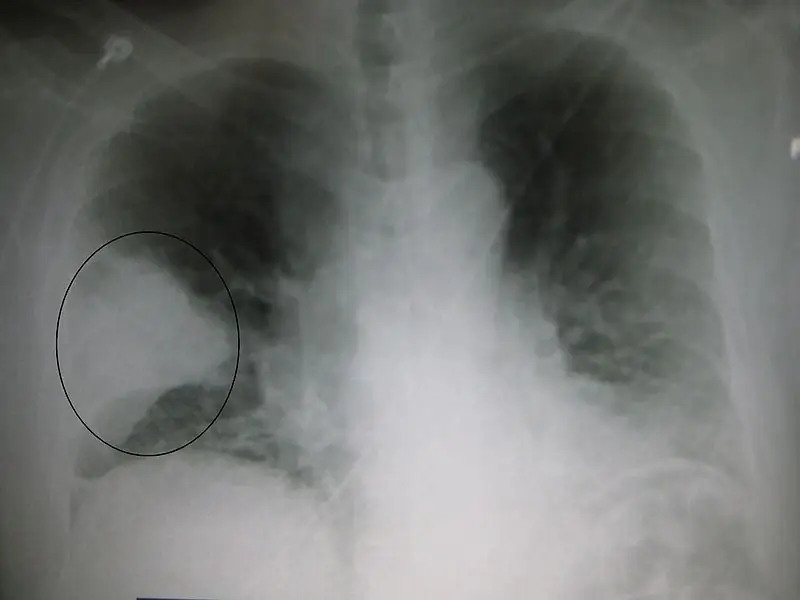

- Рентген грудной клетки показывает области консолидации и может дать полезные подсказки для определения возбудителя.

Рисунок 01: Внешний вид рентгеновского снимка грудной клетки при долевой пневмонии